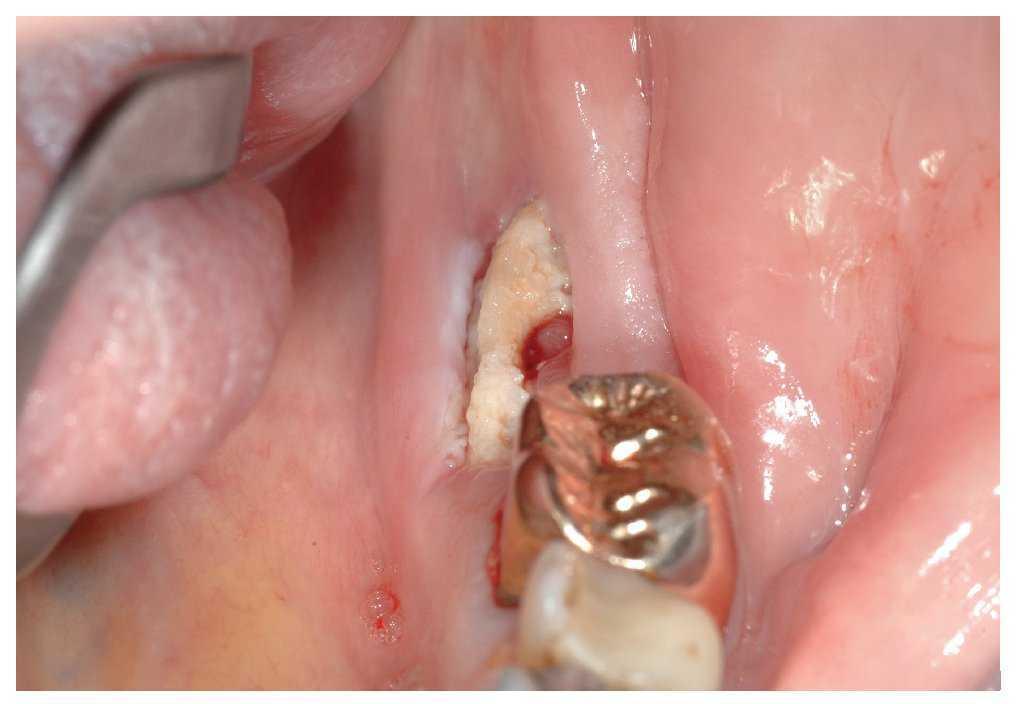

El signo clínico característico de la osteonecrosis asociada a bifosfonatos es un hueso de color blanco amarillento expuesto en el maxilar y/o en la mandíbula. El sondaje del hueso expuesto no suele provocar hemorragias y, por regla general, el paciente está asintomático22. No obstante, en áreas óseas extensas denudadas se pueden producir infecciones secundarias con un cuadro que incluye inflamación, producción de pus y dolor17. En pacientes dentados, la osteonecrosis imita a veces inicialmente un cuadro de periodontitis marginal. Después de la extracción, la cicatrización evoluciona de forma tórpida acompañada de una exposición ósea progresiva (figs. 1a a 1c). Una región afectada frecuentemente en la primera fase de la osteonecrosis asociada a bifosfonatos es la cortical lingual de la región de los terceros molares inferiores (figs. 2a y 2b). En los pacientes edéntulos se afectan a menudo zonas de la cresta alveolar maxilar y/o mandibular expuestas a la presión masticatoria directa de las prótesis totales (figs. 3a a 3c, 4a y 4b).

Figura 4a. Radiografía panorámica de un paciente de 64 años con carcinoma de próstata metastatizado. El paciente recibe tratamiento con bifosfonatos intravenosos (Zometa) desde 2005. El paciente es portador de una prótesis total desde hace varios años. En junio de 2007 experimentó una sensación de presión debajo de la prótesis en la región mandibular izquierda, que no desapareció después de varios intentos de ajuste por el protésico dental. En julio de 2007, el odontólogo de cabecera remitió al paciente al servicio de urgencias de nuestra clínica.

Figura 4b. Se observó una dehiscencia de tejidos blandos con exposición ósea superficial en el sector postero-inferior (región 34 a 36 hacia vestibular).